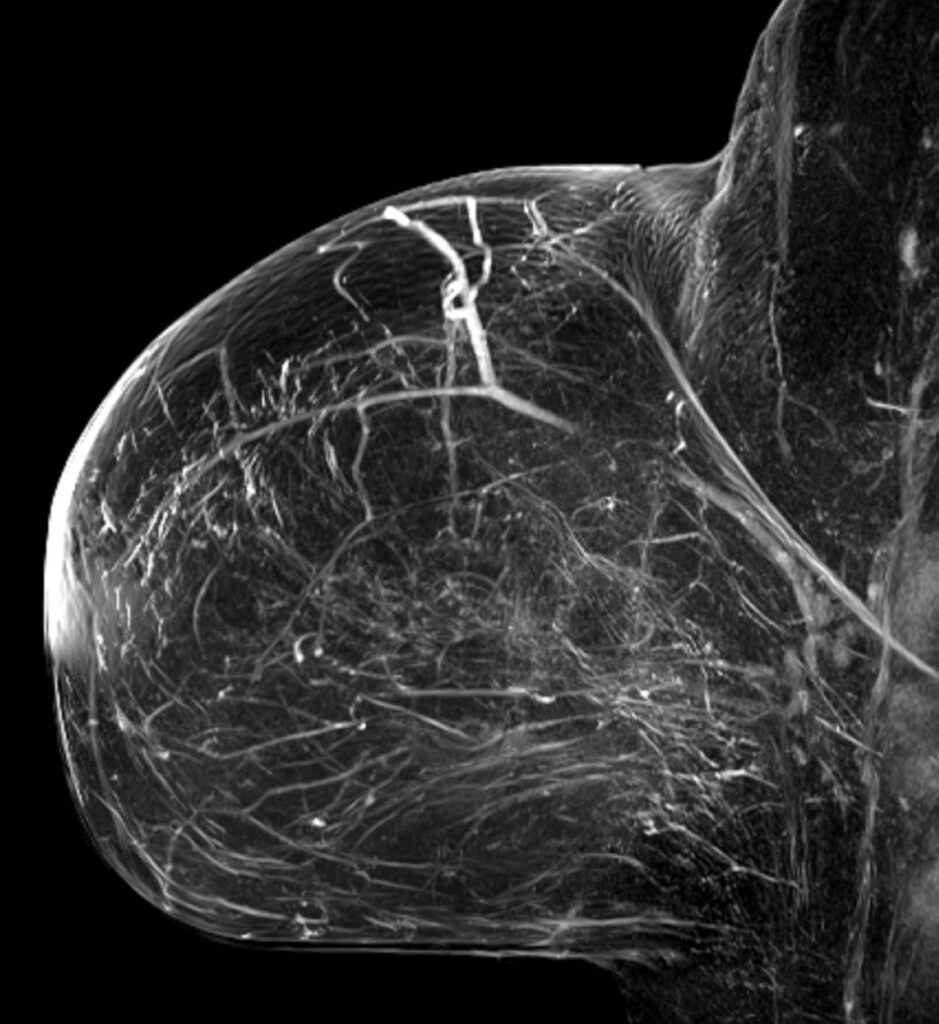

Konnten die klinische Untersuchung, die Mammographie und die Mammasonographie keine eindeutigen Ergebnisse liefern, kann als Ergänzung die Magnetresonanztomographie (MRT) herangezogen werden. Die hohe räumliche Auslösung kann dabei helfen, bereits sehr kleine Herde in der Brust erkennbar zu machen.

Hier zu sehen sind Bilder einer Brust MRT / Mamma MRT.